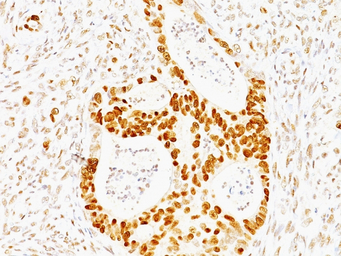

IHC-P analysis of human colon carcinoma tissue using GTX34935 p53 antibody [TRP/817].